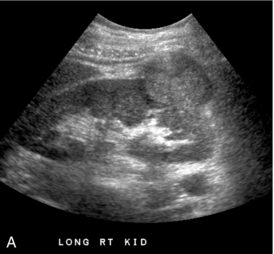

Опухоли почек

Ультразвуковое исследование в оттенках серого является основным ультразвуковым методом обнаружения опухоли почки, но цветная допплерография может предоставить дополнительную информацию для планирования хирургического вмешательства. Цветная допплерография может быть полезна при интраоперационных ультразвуковых исследованиях при попытке точно определить глубину инвазии опухоли ( рис. 9-9 ). Цветная допплерография также может быть полезна для подтверждения степени инвазии почечноклеточной опухоли в нижнюю полую вену ( рис. 9-10 ). Это может быть полезно для планирования хирургического вмешательства, поскольку четко очерчивает краниальную протяженность опухоли. Цветная допплерография может помочь подтвердить, затрагивает ли опухоль внутрипеченочную часть НПВ, что значительно усложнит хирургическое удаление. Наличие артериального сигнала внутри тромба подтверждает, что это опухолевый тромб (в отличие от мягкого тромба).